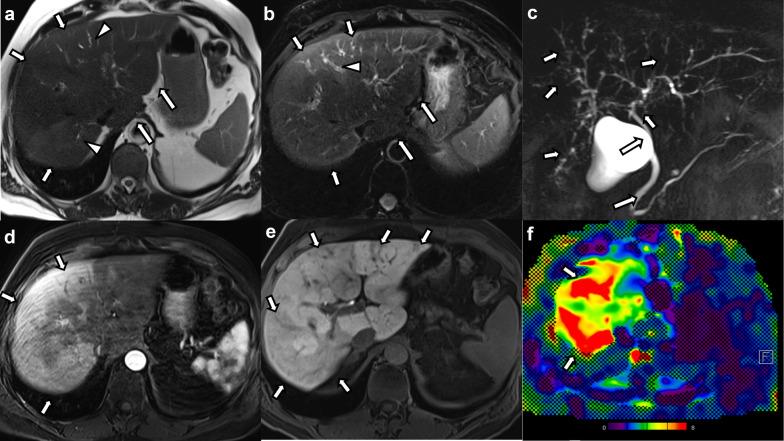

Imaging features of COVID-19-associated secondary sclerosing cholangitis on magnetic resonance cholangiopancreatography: a retrospective analysis.

Seventeen patients (mean age 60.5 years, 15 male) who underwent MRI/MRCP were included. All had been admitted to intensive care unit (ICU) (median duration of ICU stay 10 weeks, range, 2-28 weeks) and developed acute respiratory distress syndrome requiring mechanical ventilation. On imaging, all patients had intrahepatic bile duct strictures and 10 (58.8%) had associated upstream dilatation. Intrahepatic bile duct beading was seen in 14 cases (82.3%). Only one patient (5.9%) had extrahepatic bile duct stricturing. Patchy arterial phase hyperenhancement and high signal on T2- and diffusion-weighted images were seen in 7 cases (53.8%) and 9 cases (52.9%), respectively. Biliary casts were seen in 2 cases (11.8%). Periportal lymphadenopathy and vascular complications were not seen.

On MRI/MRCP, COVID-19-associated SSC presents with multiple intrahepatic bile duct strictures with or without upstream dilatation and intrahepatic bile duct beading. Surrounding hepatic parenchymal changes including alterations in enhancement and T2 signal are common. The extrahepatic biliary tree was typically spared and periportal lymphadenopathy was missing in all patients.